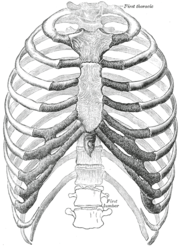

القفص الصدري جزء من الهيكل العظمي البشري يتكون الهيكل العظمى عند الانسان من الهيكل المحورى والهيكل الطرفى حيث نجد ان الهيكل المحورى يتكون من العمود الفقرى والقفص الصدرى والجمجمة . القفص الصدرى عند الانسان يتكون:

- 12 زوج من الضلوع التى ترتبط الجزء الخلفى منها بالعمود الفقرى.

- العشرة ازواج الاولى من الضلوع تتصل من الامام بعظمة القص

- الزوجان السفليان سائبان يسميان بالضلوع العائمة